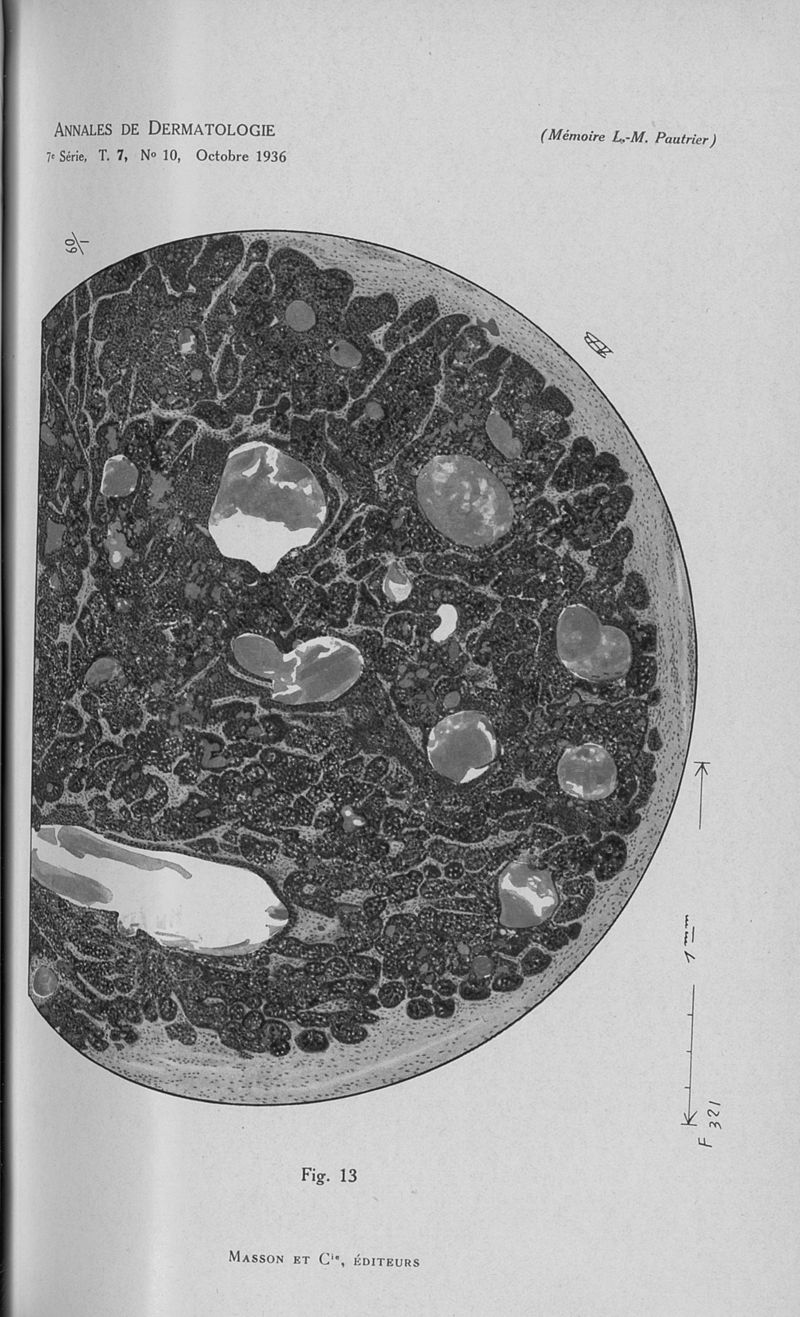

Annales de dermatologie et de syphiligraphie.

7ème série, tome VII. - Paris : Masson, 1936.